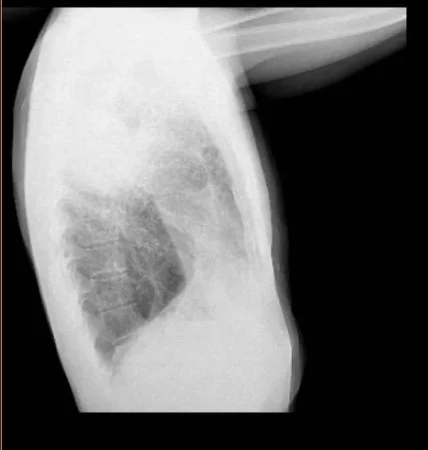

2024 09 13 12 41 58 e1726758221187 Merca2.es

Foto de unos pulmones con nódulos de un extrabajador de Cosentino facilitada por el mismo a MERCA2.